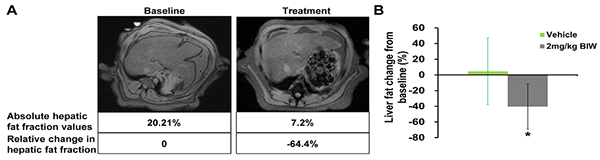

B1344對高脂飲食喂養(yǎng)的食蟹猴脂肪肝的治療作用

符合入選標(biāo)準(zhǔn)的肥胖食蟹猴接受B1344治療或?qū)φ仗幚恚?9天通過磁共振成像(MRI)測定肝臟脂肪。(A)經(jīng)每周兩次給予2 mg/kg B1344治療后的猴子肝臟脂肪含量的MRI測量結(jié)果;(B)經(jīng)每周兩次給予2 mg/kg B1344治療后的猴子肝臟脂肪含量的定量測定結(jié)果。